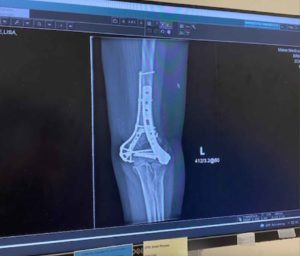

When she called me, of all her injuries, it was the broken left arm that was the most painful. Fracturing the wrist and elbow, she explained that she had Complex Regional Pain Syndrome, and described it like a sunburn, with acid being put on it. Fortunately, she had already recovered from 13 years of chronic pain with Block Therapy and knew how to breathe. She shared that this was her saving grace during the month in the hospital.

The prognosis wasn’t good. They suspected she wouldn’t walk again and never be able to have normal function with her left hand. Here are some photos showing the extent of her fractures at the time of injury.